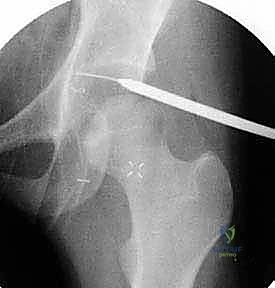

* التصوير بالرنين المغناطيسي (MRI) أو الرنين المغناطيسي مع الصبغة (MRA): يُعد الرنين المغناطيسي، خاصة عند حقن صبغة تباين داخل المفصل، المعيار الذهبي لتقييم الأنسجة الرخوة. يمكنه إظهار تمزقات الشفا الحقي بدقة متناهية، وتقييم جودة الغضروف المفصلي، واكتشاف أي التهابات مصاحبة.

* التصوير المقطعي المحوسب (CT Scan) ثلاثي الأبعاد: في الحالات المعقدة التي تتطلب تخطيطاً جراحياً دقيقاً، يُستخدم التصوير المقطعي لبناء نموذج ثلاثي الأبعاد لمفصل الورك، مما يسمح للدكتور هطيف بتحديد كمية العظم الزائد الواجب إزالتها بدقة ميكرونية.